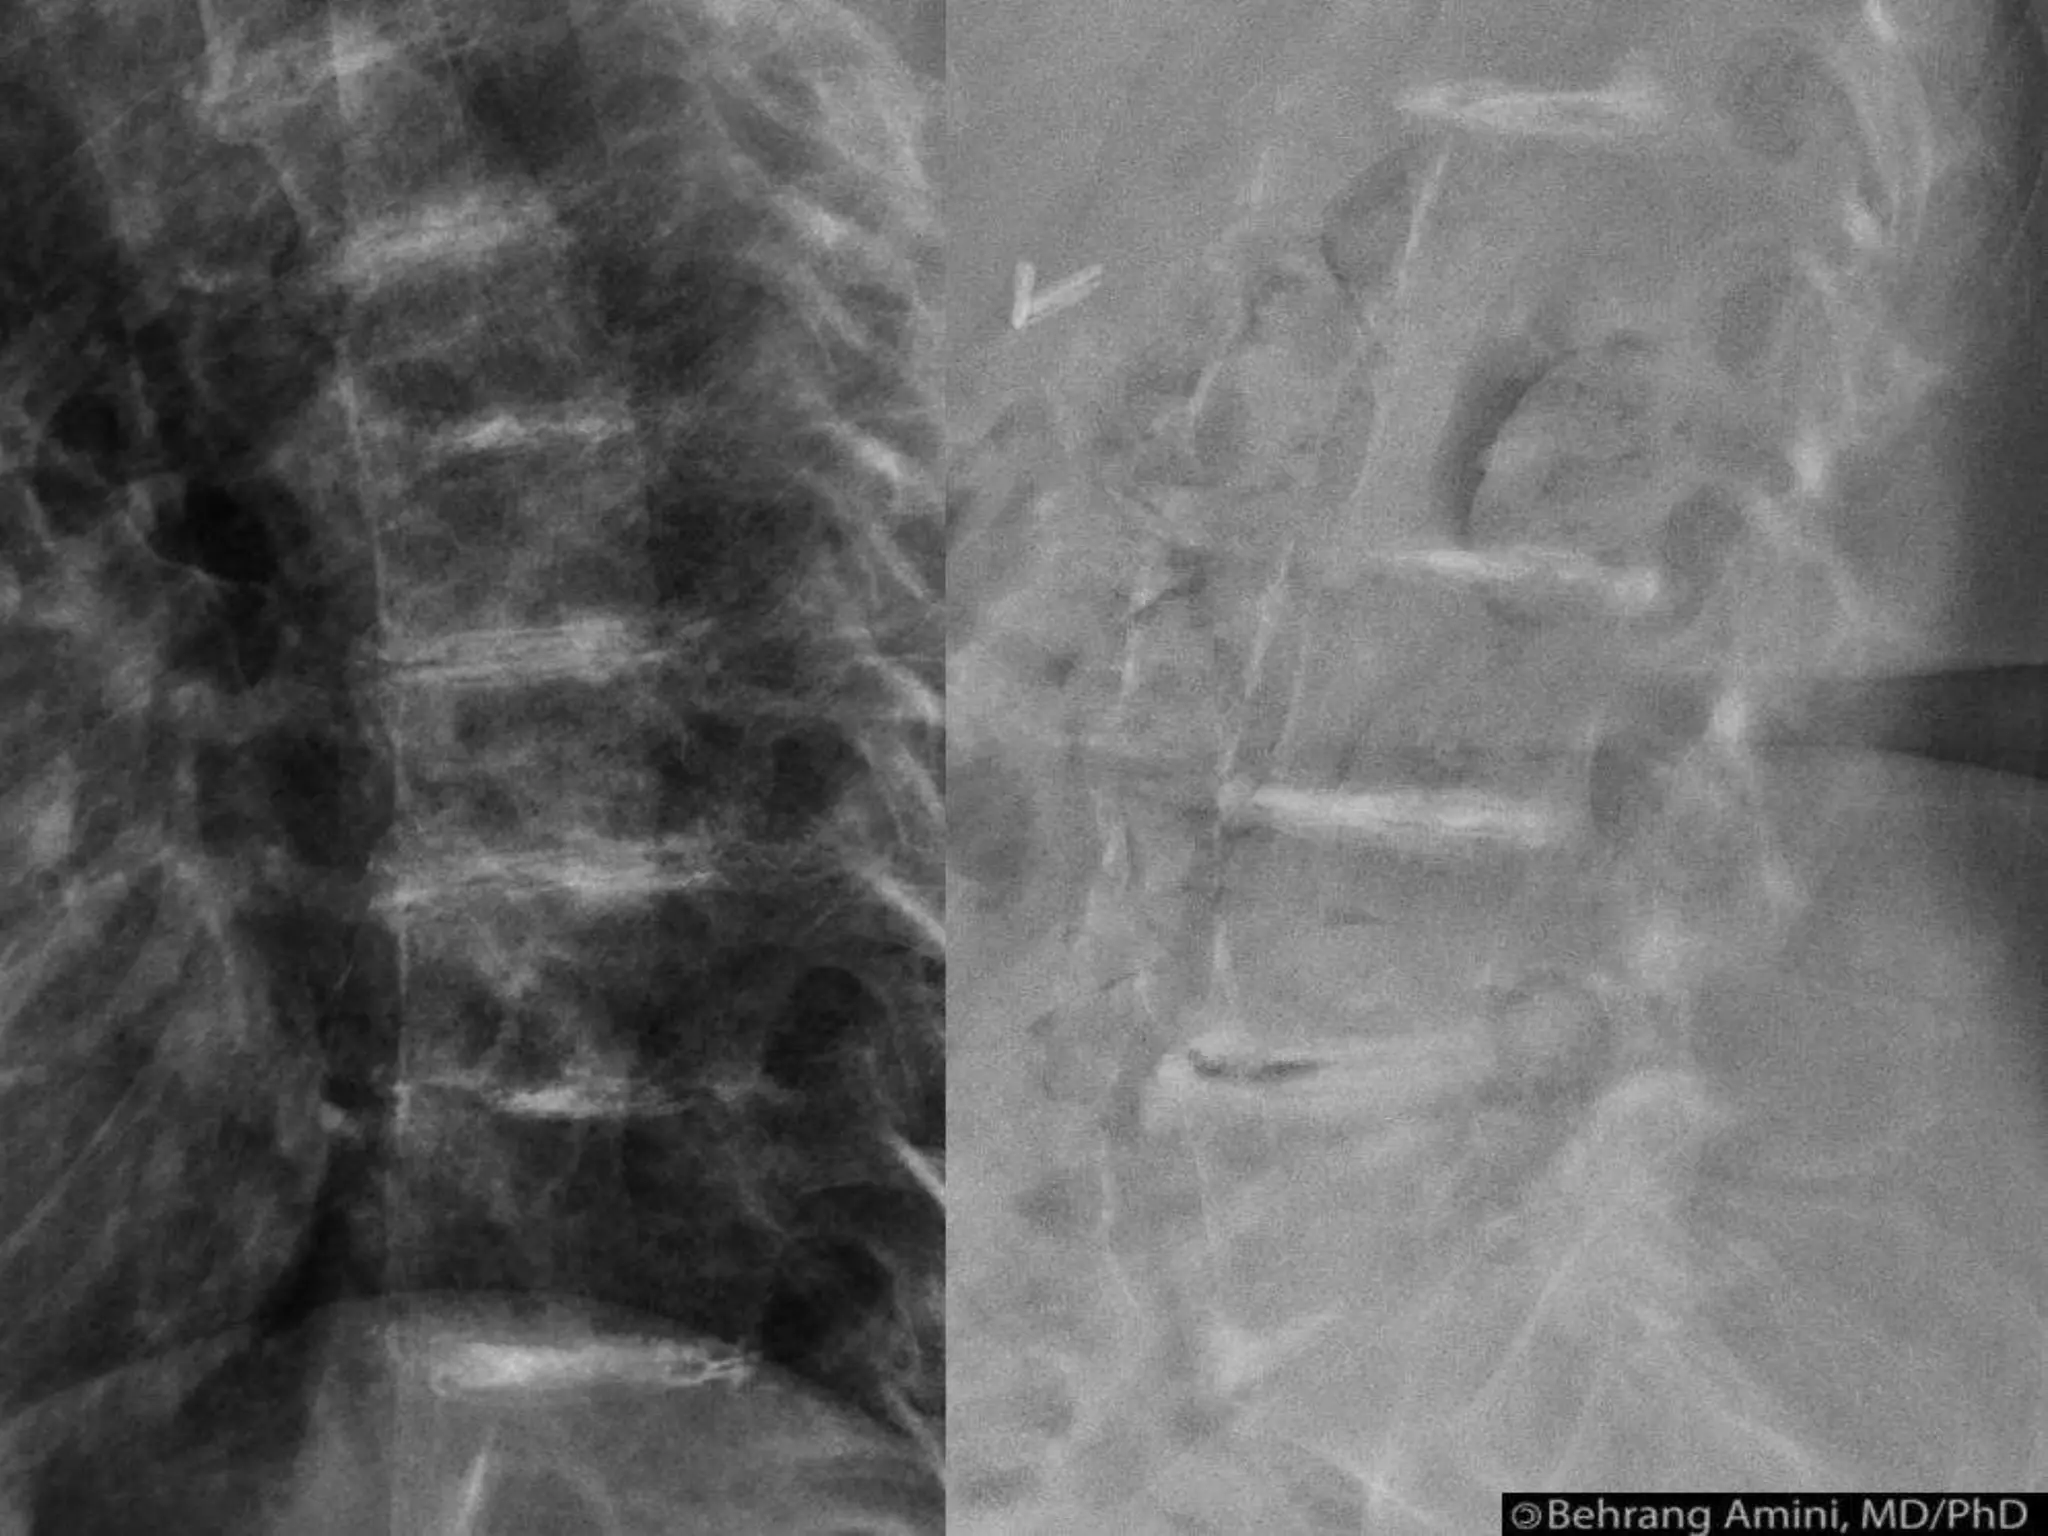

Vertebral anamolies (scalloping of posterior

aspects of vertebral bodies, erosion of

pedicle,pencilling of ribs, i.v. foramin

enlargement)

NEUROFIBROMATOSIS • Commonest genedisorder affecting skeleton • Type 1 (NF 1) = VON Reckling hausen’s disease • (abnormality is in the gene which codes for neurofibromin on chromosome 17) characteristic lesions are --- schwann cell tumors(neuro fibromata) patches of skin pigmentation (café-au-lait spots)

• 133.

Type 2 rare(gene defect which codes for schwannomin on chromosome 22) Scoliosis & soft tissues overgrowth (elephantiasis) Vertebral anamolies (scalloping of posterior aspects of vertebral bodies, erosion of pedicle,pencilling of ribs, i.v. foramin enlargement)